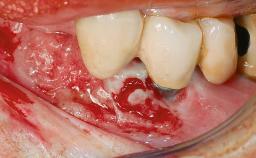

A 73-year-old woman was referred to the Division of Periodontology (University of Geneva School of Dental Medicine) after repeated unsuccessful treatment of a peri-implant infection. She was systemically healthy and did not smoke. The patient’s history revealed that, three years earlier, an immediate implant (Straumann Tapered Effect RN 4.8/4.1; Institut Straumann AG, Basel, Switzerland) had been inserted to replace the upper right central incisor. A metal-ceramic crown had been delivered using an adhesive resin cement. One year later, the patient had consulted another dentist due to discomfort in the soft tissues in the implant region. There was a suppurating peri-implant pocket, 10 mm deep. Peri-implant bone loss and excess luting cement were seen on the radiograph. The situation was treated with non-surgical debridement, amoxicillin, and repeated submucosal irrigation with a chlorhexidine digluconate solution. The patient was referred after the suppuration had persisted for several months.